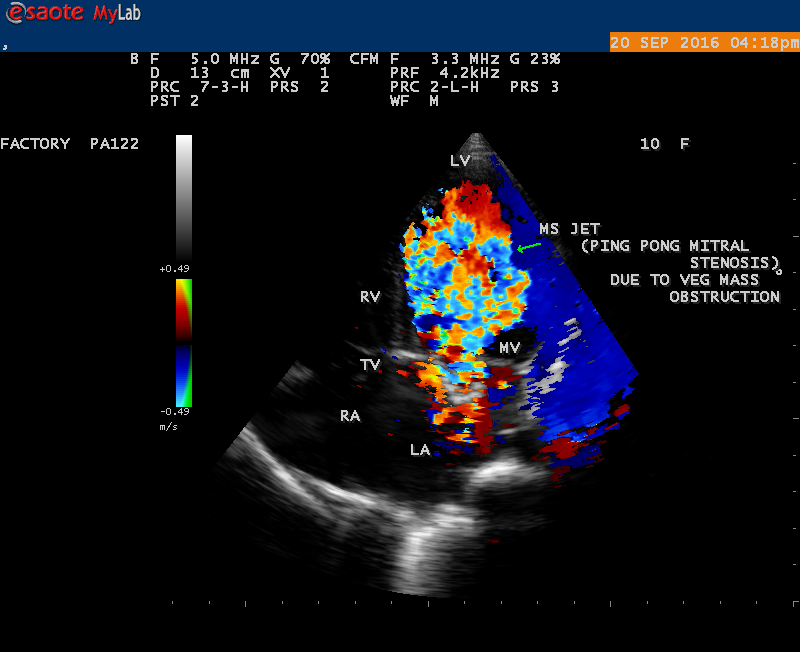

The most common and direct evidence of infective endocarditis is the vegetation and it begins as a microscopic focus of infection and gradually grows into a conspicuous mass. It is typically an irregularly shaped, highly mobile, echogenic mass attached to the free edge of a valve leaflet ( most commonly at the coaptation line) and tends to develop on the ‘upstream’ side of the valve leaflets ( ie, the ventricular side of aortic valve and the atrial side of mitral and tricuspid valves. They may be seesile or pedunculated, but usually has an oscillating or fluttering motion, a typical feature of most vegetations. Vegetation move with the leaflet in a more chaotic (‘oscillating’) manner and it may prolapse through the valve into the LV (left ventricle) as it opens as shown in Figures 3, 4 and 16 and into LA (left atrium) as it closing (Figure 5 and 6) . The mass of vegetation is typically homogeneous with echogenicity similar to that of the myocardium. The infectious process often alter the valvular structure and function. Extensive involvement of the leaflet may result in chordal rupture, leading to severe regurgitation as shown in Figure 21 . Direct and typical signs of RMCT (ruptured mitral chordate tendineae) were chain-flail or whiplash-like changes and had an incidence of 86.7%, causing severe regurgitation and mitral chordal rupture is the leading cause of flail mitral leaflet[30]. A large vegetation may obstruct the valve orifice as shown in Figure 1 and 2 , sometimes termed as “obstructive-type bacterial endocarditis” and producing a functional valve stenosis ( Ping-Pong mitral stenosis [31]) similar to left atrial myxoma as shown in Figure 29.

The size and shape of vegetation vary due to curling of vegetation. The size of vegetation in this child is 35.6 x 9.3 mm as in Figure 17 , 20 x 23.7 mm as in Figure 1 , 32.9 x 13.9 mm as in Figure 2 .

The shape of vegetation varies in this child as ‘popcorn’ like (Figures 1,3 and 4 ), rod-shaped (Figure ), basket shaped (Figure 7 )[33-Figure 13.3], ‘baby in hand’ appearance (Figure 18), ‘cucumber shaped (Figure 2 ) and a ‘bunch of plantain’appearance (Figure 33 ), ring shaped (Figure 19 }, bileaflet structure (Figure 9 )with bileaflet MR jet as shown in Figure 10 . and kissing forms (Figure 13 - parasternal long axis view, Figure 14 - apical four chamber view and Figure 15 - short axis view)